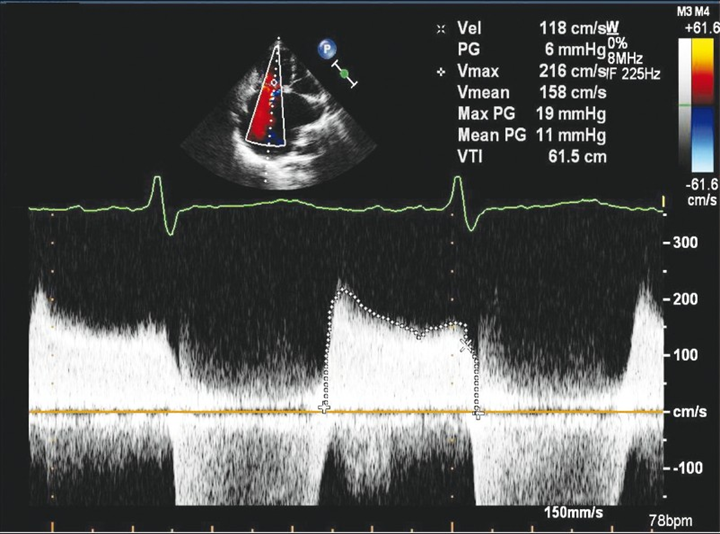

asses in Spectral doppler

Tv Inflow (PW)

RV inflow pattern

PWD gate at tips of TV leaflets

Normal Flow is Antegrade

Use TV package (E/A velocity)

Measure peak E velocity and Decel slope

>1 m/s suggestive of high velocity

2. Measure peak A wave